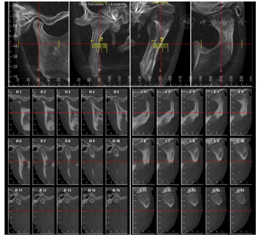

治疗前CBCT检查(图6):左侧髁突膨大,突出关节窝内,骨质密度降低

3.正颌外科完成左侧髁突切除及双颌手术:Le fort Ⅰ型截骨后摆正上颌平面(图9A),经导航完成左侧髁突切除(图9B),术中可见翼外肌纤维占据关节窝,髁突难以按照数字设计复位至关节窝内(图9C)。术后即刻CBCT显示咬合平面摆正,左侧髁突切除后升支骨段未能实现数字化设计的复位(图10)。

5.密切关注左侧关节复位情况,在正畸治疗的引导下左侧关节逐渐恢复髁突形态,并复位至关节窝内,在术后12个月时改建形成类髁突样形态(图12)。术后12个月时进行下颌运动轨迹记录,开口型轻度左偏,开口度正常,双侧颞肌肌力基本一致,左侧咬肌肌力较右侧弱(图13)。